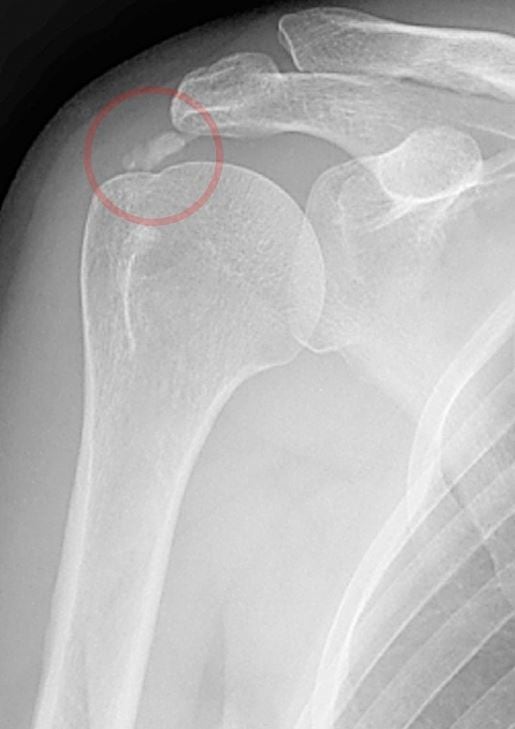

어깨는 관절 활동량이 많고 활동량이 많은 부위로 석회화건염이 잘 발생하는 부위입니다. 어깨의 석회화건염은 칼슘 성분이 축적되면서 염증과 통증 증상이 나타나는 질환이다. 적절한 치료를 하지 않으면 염증의 범위가 넓어지고 석회석의 크기가 커져 회전근개파열이나 오십견 증상이 나타날 수 있습니다. 하는 것이 좋습니다. 석회성 어깨 건염은 통증이 시작된 초기에 운동 요법과 같은 비수술적 방법으로 치료할 수 있습니다.

#어깨석회성건염과 도수치료를 꾸준히 하시면 어깨 주변의 연조직을 이완시켜 잘못된 자세를 교정하고 어깨 근육을 강화시켜 통증 증상을 줄일 수 있습니다. 하지만 석회가 상대적으로 크고 어깨 석회화 건염의 통증이 심하거나 자주 재발한다면 # 肩석회 건염 수술법을 시행하여 석회를 제거하는 것이 좋습니다. 어깨 석회화 건염의 원인은 반복되는 어깨 움직임이나 순간적으로 어깨에 많은 힘을 가하는 동작으로 어깨 관절에 과부하가 걸리면 어깨 힘줄에 산소 공급이 부족해 힘줄이 손상되고 석회석이 쌓이는 것이다. 어깨에. 힘줄 조직은 나이가 들면서 퇴행성 변화, 힘줄 세포의 괴사, 운동 부족, 잘못된 자세 또는 생활 방식으로 인한 석회석 축적으로 이어지는 혈관 손실이 발생합니다.

어깨 석회화 건염은 어깨 관절 앞쪽에서 시작하여 팔이나 목 아래로 확장되는 어깨 열상이 반복적으로 발생하는 등 극도로 고통스러운 증상을 일으키는 질환입니다. 견봉 주변의 압통, 심한 야간 통증 증상은 수면 장애를 유발할 수 있습니다. 팔을 들어 올리거나 한쪽으로 돌리기가 어려운 고통스러운 증상. 파악 후 그에 상응하는 치료방법을 시행하고 있습니다. 치료는 석회화 건염에서 통증의 크기, 특성 및 위치에 따라 달라지며, 석회화의 크기가 완화를 제공합니다.

비수술적 방법으로 통증 증상이 호전되지 않거나 통증 증상이 빈번하고 심할 경우 어깨 석회화 건염의 수술적 방법을 이용하여 석회를 제거해야 합니다. 어깨 석회화건염 수술은 피부에 약 5mm 정도의 작은 절개를 하고 내시경과 수술 기구를 삽입해 인설을 제거하고 회전근개 결손이 있을 경우 봉합하는 것이다. 흉터가 거의 남지 않아 회복이 빠르고 만족스러운 치료 결과를 얻을 수 있습니다. 수술 후 회전근개 재발을 예방하기 위해서는 어깨의 석회화건염에 대한 운동을 지속하여 어깨 근육의 근력과 인대의 유연성을 향상시킬 수 있는 것이 좋으며 정기적인 검사가 필요합니다.